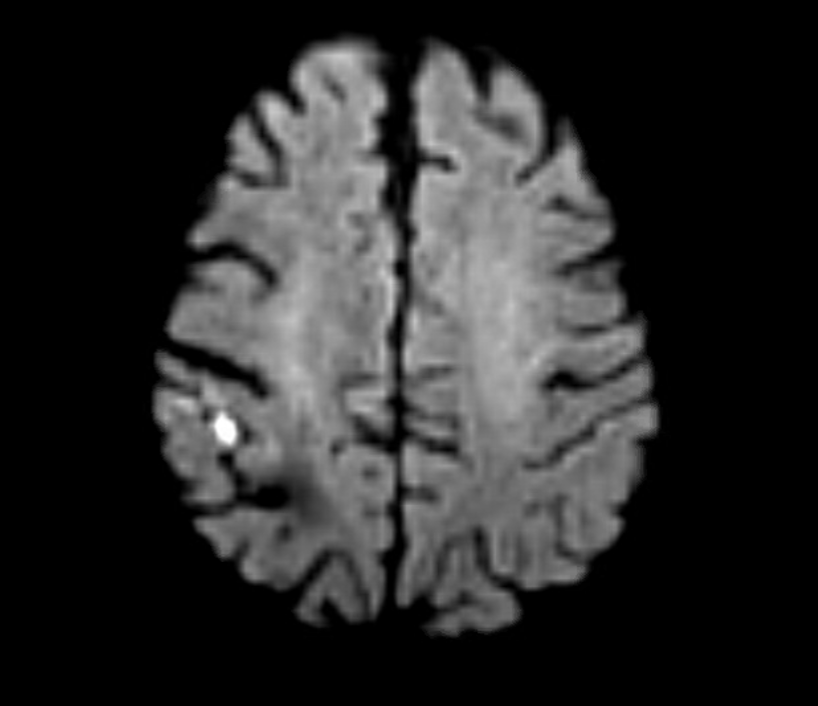

MRI confirmed a right hemispheric infarction and operation was planned.

Right sided embolic stroke in MCA distribution